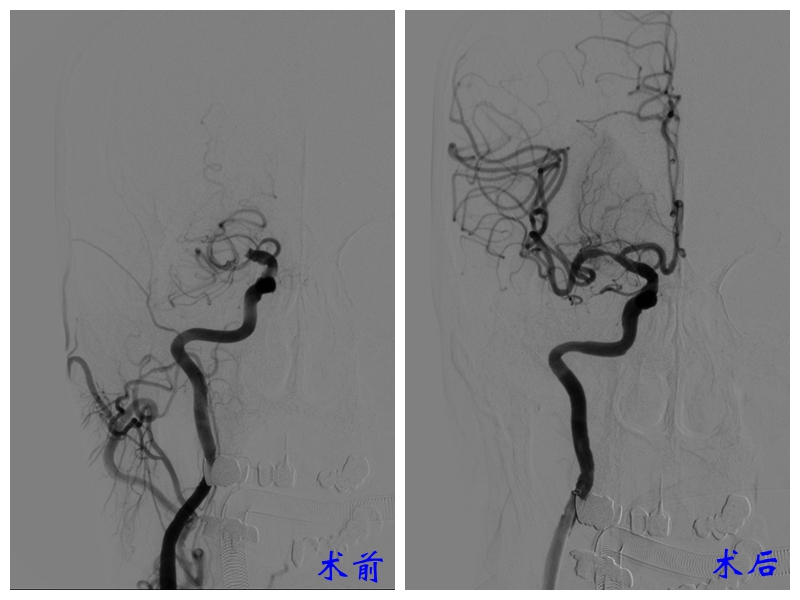

确诊患者脑梗塞后,神经外科主任曾怀文、副主任高潮带领介入团队紧急为其开展了“脑血管造影术+经皮颅内动脉取栓术”。

术中可见,患者右侧颈内动脉末端大脑中动脉起始部完全闭塞,右侧大脑中动脉及右侧大脑前动脉远端分支不显影。

手术顺利完成,王大爷的左侧肢体肌力从入院时的3+级恢复至5级。